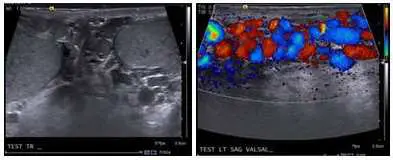

48 歲男性病⼈主訴左腹股溝脹痛,超⾳波掃描如附圖,最可能診斷為下列何者?

影像為雙版面超音波,左側為灰階(gray-scale)影像,右側為彩色都卜勒(Color Doppler)影像,標示「TEST LT SAG VALSAL...」(左側睪丸縱切面,Valsalva 操作中)。

左側灰階影像:

- 可見多條迂曲、管狀、無回音(anechoic)的管道結構,聚集於睪丸上方及旁邊,代表擴張的蔓狀靜脈叢(pampiniform plexus)。

- 管徑明顯大於正常(正常蔓狀靜脈叢管徑 < 1.5 mm,靜脈曲張診斷閾值 ≥ 3 mm)。

右側彩色都卜勒影像(Valsalva 操作):

- 可見大量紅色(red)及藍色(blue)彩色血流訊號充填於多條擴張靜脈內,紅色代表血流朝向探頭,藍色代表遠離探頭。

- 在 Valsalva 操作時訊號更加明顯,代表靜脈逆流(venous reflux)陽性,符合精索靜脈曲張診斷標準(逆流 > 2 秒)。

- 這是精索靜脈曲張彩色都卜勒的典型表現。